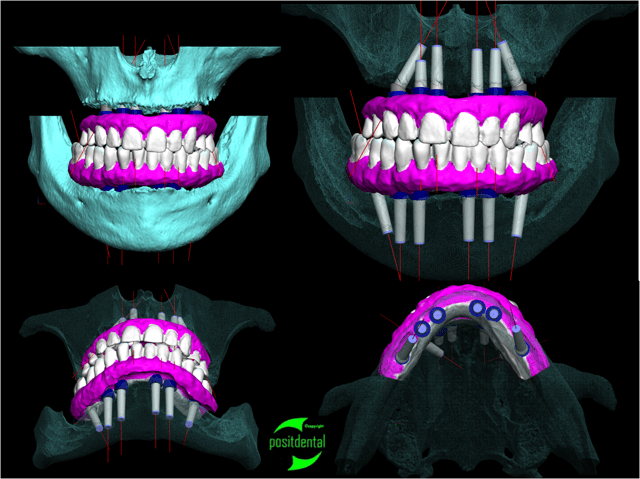

Pour la réalisation d'un all on 6 haut et bas avec MCI durant la même opération , je fabrique un renfort en inox pour la prothèse provisoire. Ainsi on obtient un ensemble transitoire parfaitement rigide.

Je réalise l'ensemble, guide chirurgical de forage, positionneur d'implants et armature du provisoire à partir des images native DICON du scanner. Dans ce cas la chirurgie et la mise en fonction de la prothèse transitoire ont été effectuées en une opération.

Pour réaliser ce travail j'ai eut besoin du montage haut et bas sur cire.

1 je confectionne un guide radiologique.

2 après le scanner le patricien garde les planches et m'indique l'emplacement et le choix des implants et m'envoie le CD du dentascan

3 par e-mail je retourne l'étude avec des coupes, mise en situation et densité osseuse qui permettent d'évaluer la fixation primaire et la stratégie du forage

4 le guide, le provisoire, la reconstitution osseuse en stéréo lithographie, le tout fabriqué au labo puis livré avec un délai suffisamment nécessaire avant l'intervention pour être contrôlé physiquement et le guide inox stérilisé.

la réussite chirurgicale de cette intervention revient au Docteur Jean KOSKIEVIC (Paris).